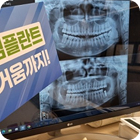

광진구에서 만나는 전문적인 장비와 진료

연세원드림치과는 전문적인 장비와 진료 시스템을 통해

안전하고 편안한 진료 환경에서

환자 맞춤형 수준 높은 진료를 진행하고 있습니다.